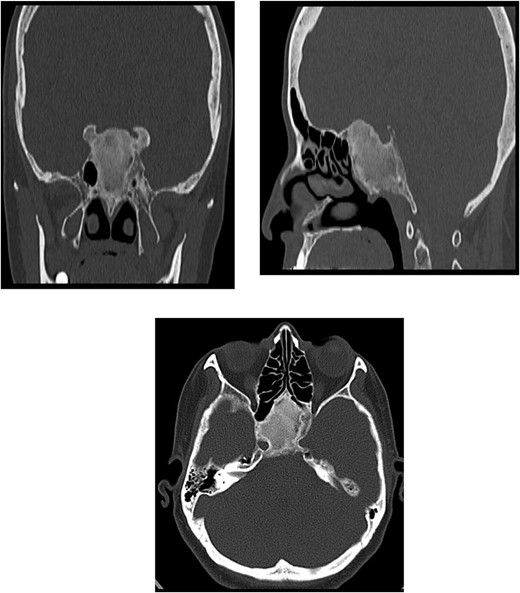

A 56-year-old female presented with a 1-year history of intermittent headaches, which had been increasing in severity and intensity over the last 2 months. The headache was mainly in the right parietal region, throbbing in nature and did not display diurnal variation. The severity of the headache was stated as 7–8 degrees on the Numerical Rating Pain Scale (NRPS; [6]). The pain was partially relieved with analgesia (acetominophen and ibuprofen). She also complained of mild right nasal congestion and intermittent mild otalgia. Physical examination was normal apart from nasal septal deviation. Computed tomography (CT) of the paranasal sinuses showed expansion of the sphenoid bone demonstrating diffuse ground-glass matrix and sclerosis obliterating the sphenoid sinus cavity (Fig. 1). Magnetic resonance imaging (MRI) was highly suggestive of fibrous dysplasia of the sphenoid bone, which appeared as expanded mass with dark T2 signal and T1 hypointense signal (Figs 2 and 3). Near-total excisional biopsy was performed using endoscopic transeptal approach to sphenoid sinuses. Histopathological examination of several pieces of greyish tan and brown bony tissue measuring 3.5 × 2.5 × 1.7 cm. showed branching irregular trabeculae of woven bone with intervening hypocellular fibrous stroma, consistent with a diagnosis of FD (Fig. 4). The patient’s headaches improved greatly following surgery. Two years post-op she reports infrequent headache with a severity of 2 on NRPS.

Coronal T1 image showing the expansion of the clivus with heterogeneous predominantly low T1 signal. Axial flair images showing the anteroposterior (AP) extension of the mass lesion with obliteration of the sphenoid sinuses. The cavernous portions of both internal carotid arteries (ICAs) have signal void intensity suggesting patency.